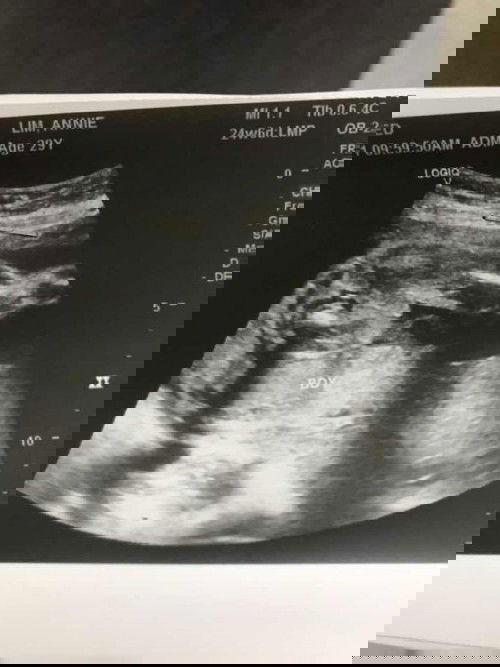

ganyan din sakin kitang kita ang pototoy nya. 2 times nakita sa ultrasound then kinonfirm din ng CAS lalaki talaga. 16 weeks palang nakita na gender nya🥰 congratulations po

kitang kita po pututuy, hindi po shy type si baby haha congrats po!

yes sis, kitang kita pototoy hehe same tayo baby boy din 🥰

same baby boy..itlog agad ung nkita🤭

yup mami it's a boy congrats ❤️

Mas madali po talaga makita pag boy